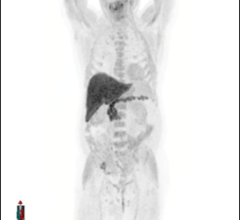

Maximum Intensity Projection 18 F Fluciclovine Pet A And 68 Download Scientific Diagram